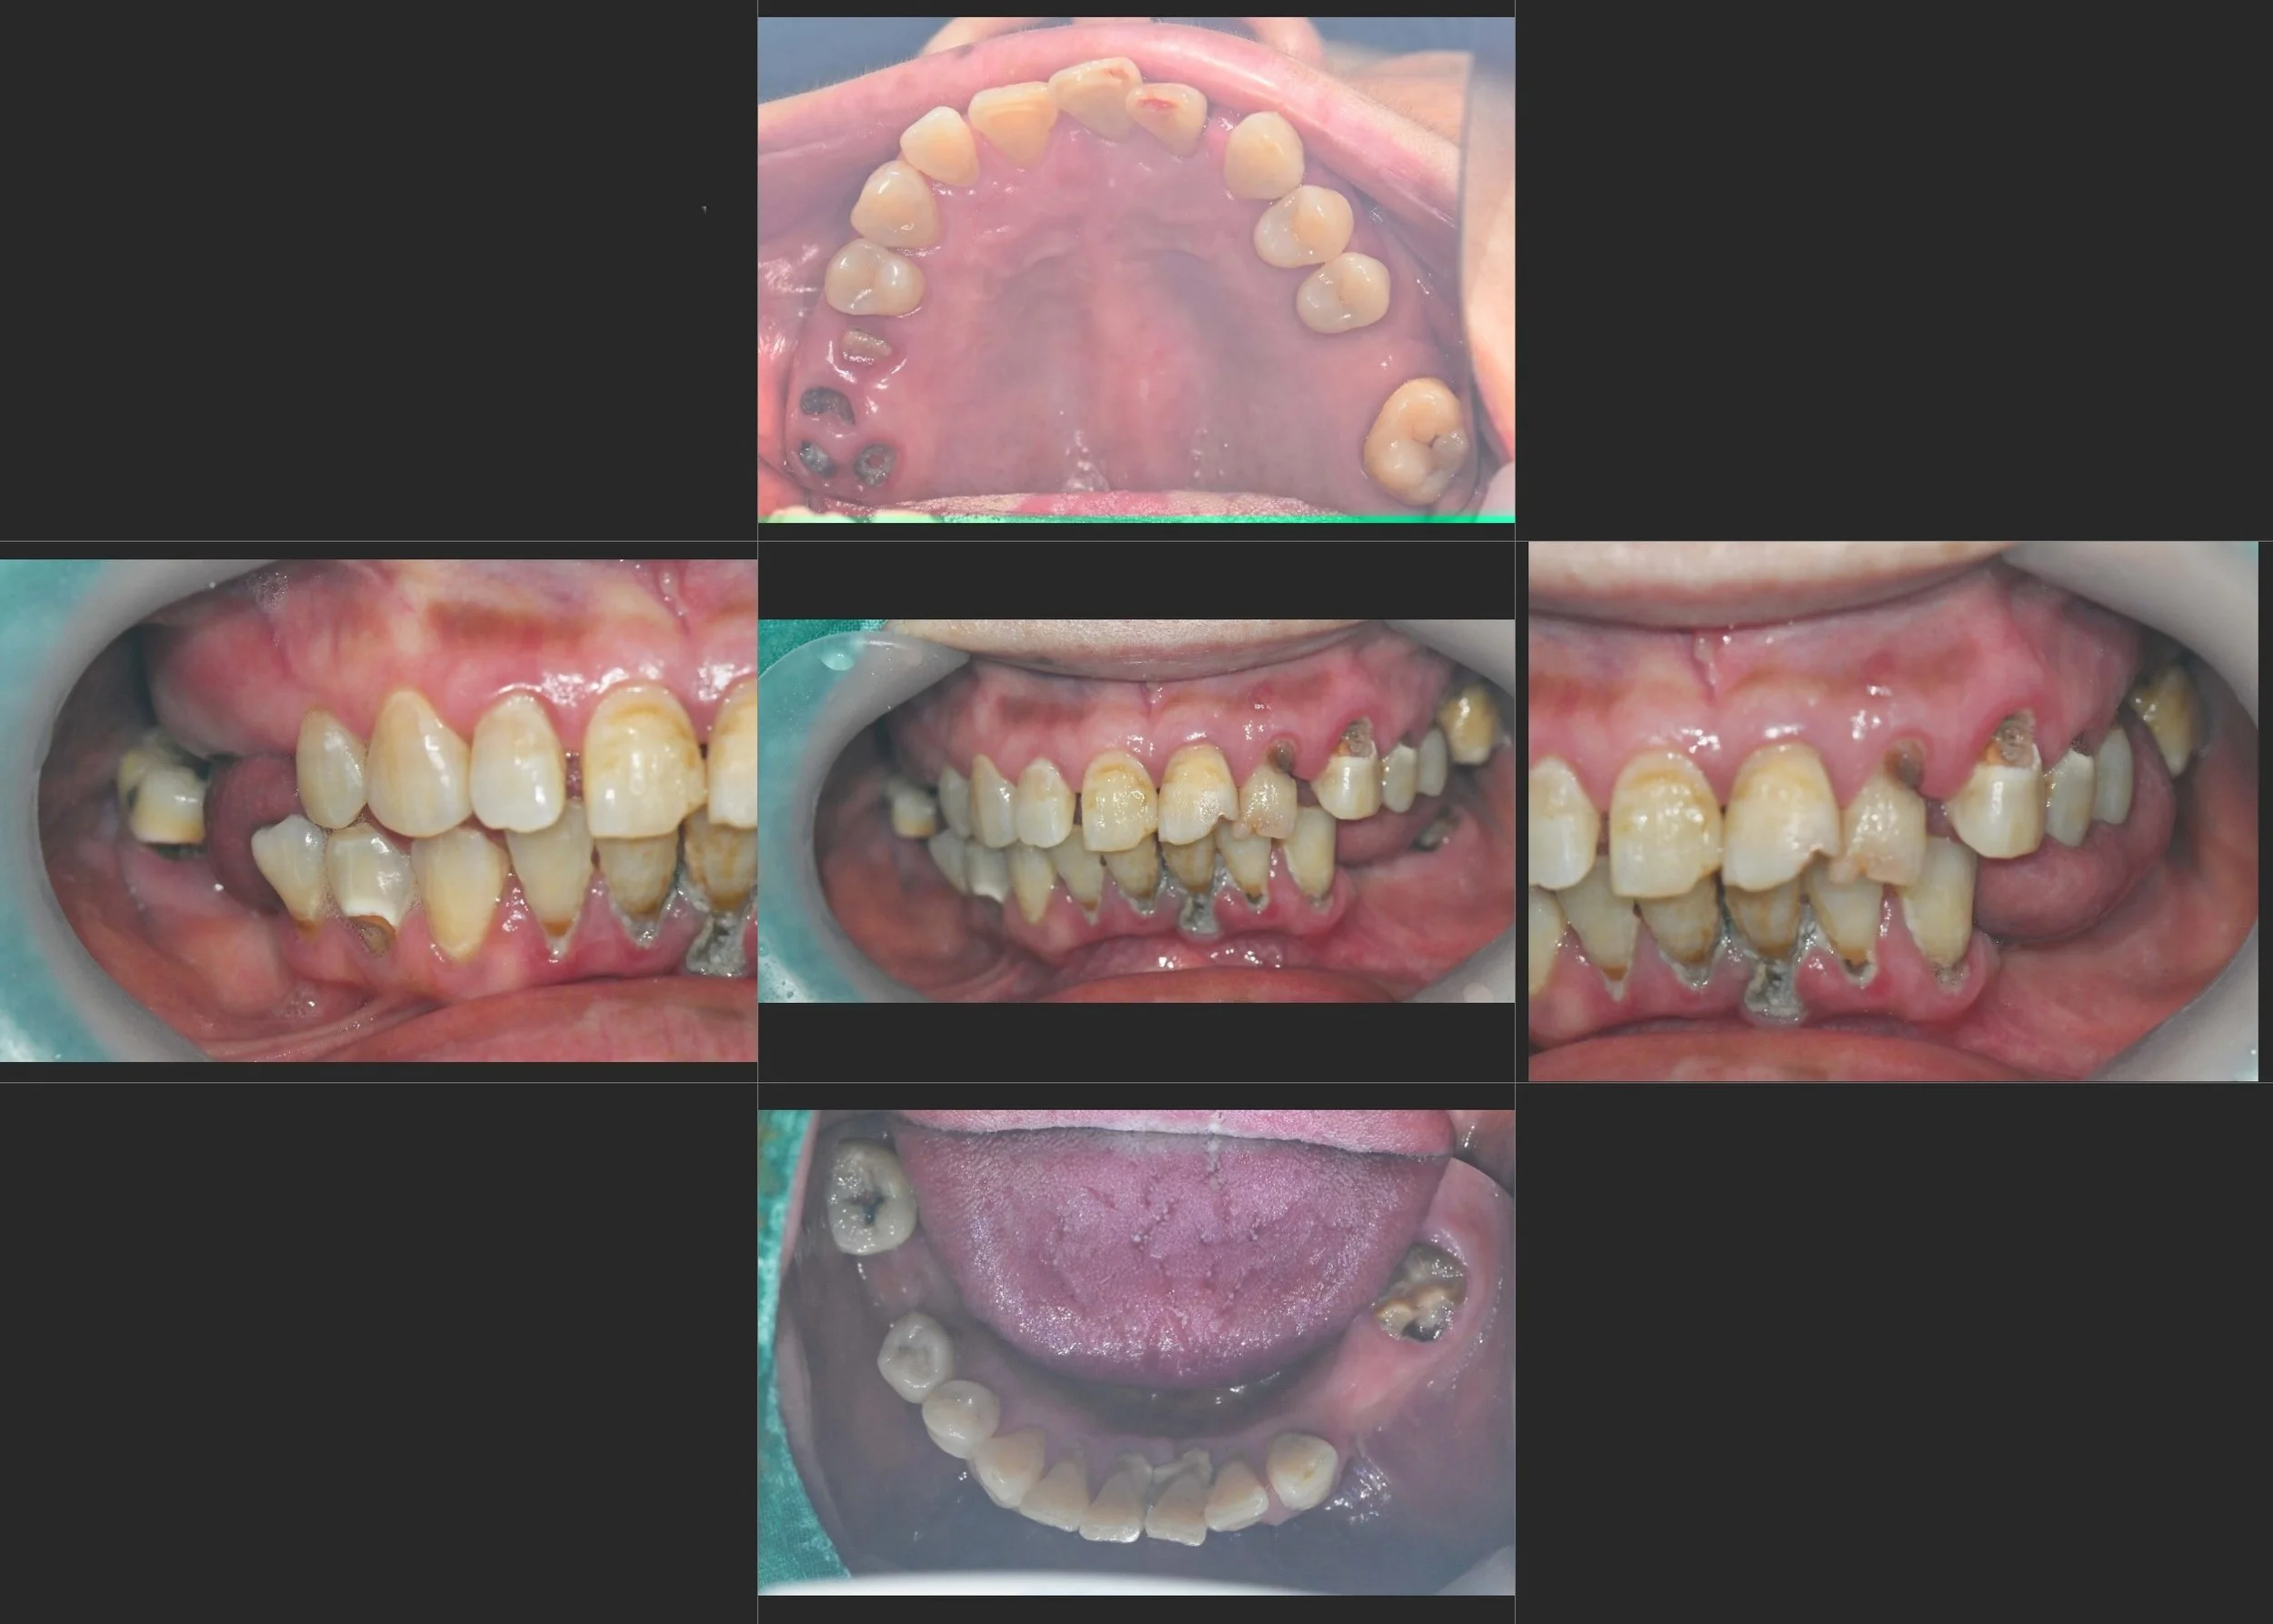

INTRA ORAL - BEFORE

A female patient in her 60s presented with a severely compromised dentition and significant functional distress. Years of generalized severe periodontitis had led to the following clinical challenges:

• Posterior Support Failure: The loss of multiple posterior teeth had caused a total collapse of the Vertical Dimension of Occlusion (VDO).

• Anterior Deterioration: Without posterior "stops," excessive occlusal forces were transferred to the anterior segment, leading to pathological wear, spacing, and progressive periodontal breakdown of the front teeth.

• Aesthetic & Functional Impairment: The patient suffered from reduced chewing efficiency and was highly self-conscious about her failing smile.